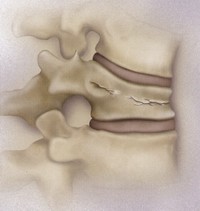

中天晟院副院兼脊椎神外科主任引了「人工骨水泥椎修融合」,手是人工骨水泥置入受之椎,化椎,增加脊椎之定性,以少病患因脊椎椎受而生的慢性疼痛。椎修融合的施行可用 皮穿刺至椎施行,或於脊椎手同施行。施前後要一、小。

中天晟院脊椎神外科表示,人工骨水泥不是真的水泥,它的成分是甲基丙烯酸酯聚合物,在手中,生只要花五分骨水泥 乾掉,就能修好病人骨折。手於一九八七年首先在法施行, 是用治脊椎椎血管瘤以防止椎被一步破,後效果良好 ,目前已被泛用於治各骨疏引起的迫性骨折。因骨疏症引起椎骨折的患者,以及因其他原性瘤,如血管瘤,骨髓瘤,移的椎瘤所引起的脊椎疼痛及椎柱不定所引起的症.主任他在庚院和偕院上百手.

在局部麻醉下,利用可整的X光找到的入,把一枝4mm治扎入椎,注入人工骨泥